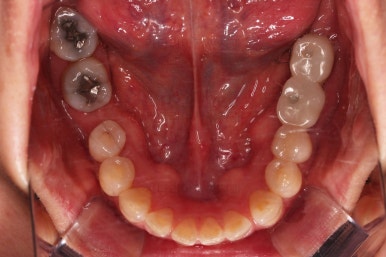

초진 시 입안의 모습입니다.

아랫니 큰 어금니 하나가 없어서 임플란트를 원하셨던 환자분이셨어요.

치아가 빠진지 오래되어 앞뒤 치아가 모두 반자리로 쓰러진 상태였어요.

그래서 큰 어금니 사이즈의 임플란트가 식립되지 못하는 상황이었어요.